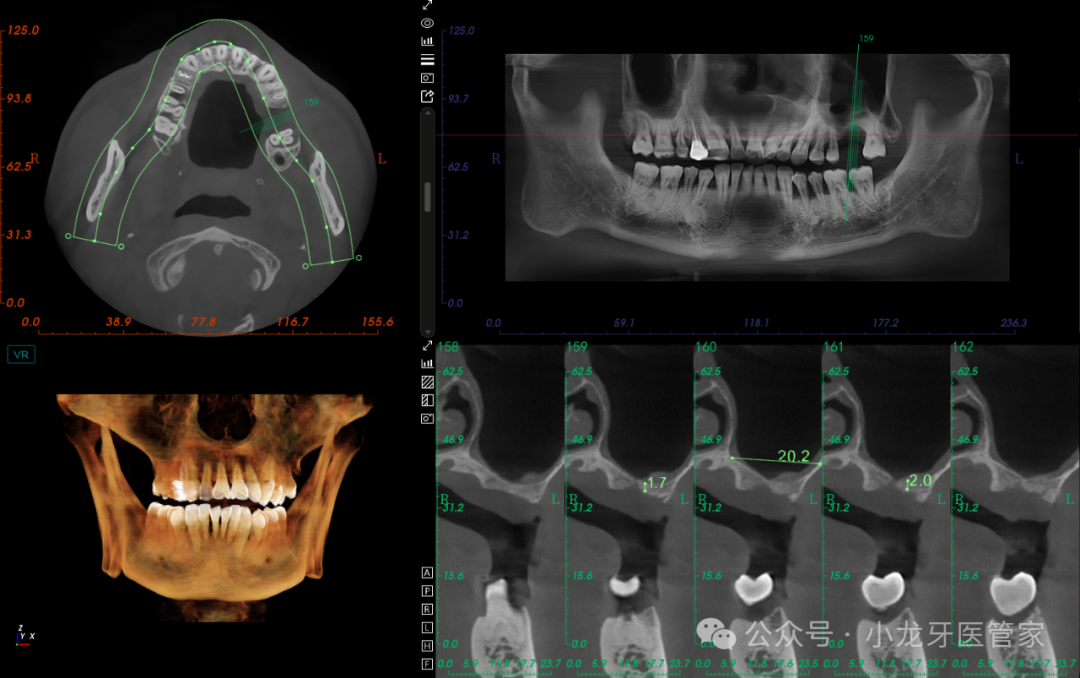

术后6个月影像学图片

(CT上再次的测量数据比之前要理想,成骨效果较好)